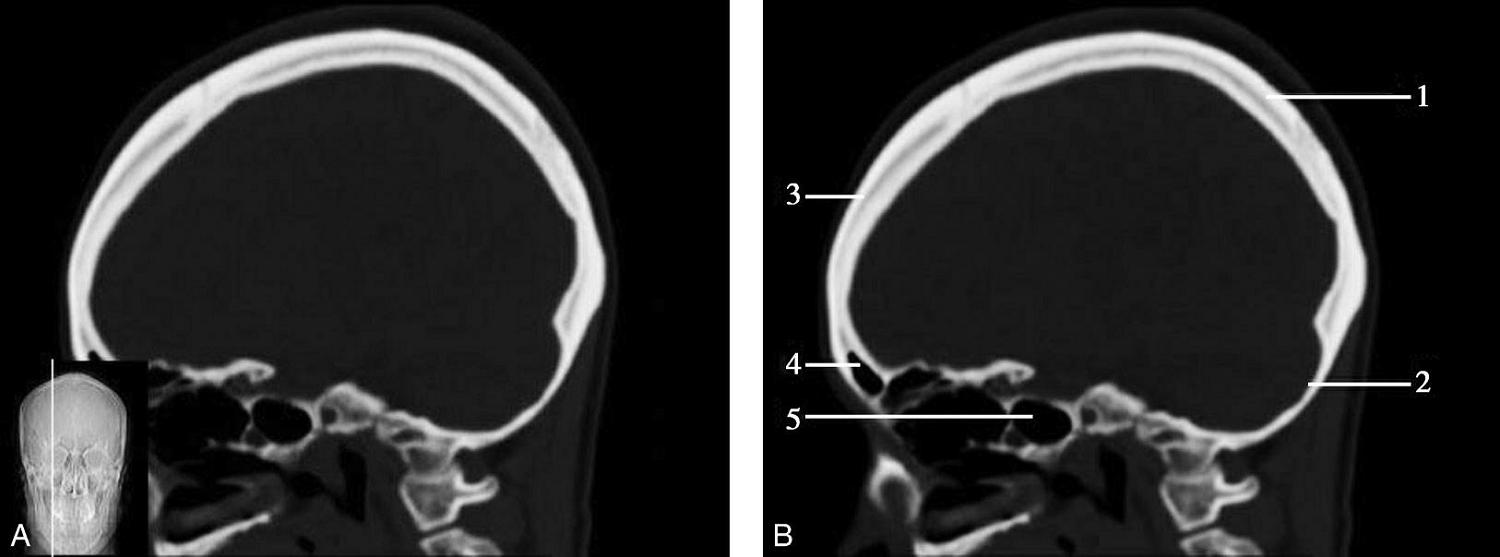

重要结构:胼胝体、垂体、中脑导水管、扣带回、中央沟、第三脑室、斜坡(图1-2-59、图1-2-60)。

图1-2-59 正中矢状面CT

A.矢状面;B.矢状面标注

1.中央沟;2.扣带回;3.胼胝体体部;4.侧脑室;5.中脑;6.胼胝体膝部;7.穹隆;8.第三脑室;9.胼胝体压部;10.垂体;11.中脑导水管;12.第四脑室;13.脑桥;14.蝶窦;15.斜坡;16.小脑扁桃体;17.延髓

图1-2-60 正中矢状面骨窗CT

1.顶骨;2.枕骨;3.斜坡;4.额骨;5.蝶鞍

此层面可显示胼胝体全貌,它位于层面中央区域,是呈上凸下凹的弧形结构,由前向后分为嘴、膝、体和压四部分。扣带回环绕胼胝体上方,扣带沟位于扣带回的上方。大脑半球中部和后部分别可见较深且恒定的中央沟和顶枕沟。中央沟为是额叶顶叶分界标志。

胼胝体下方为侧脑室及穹窿,第三脑室借穹窿与前上方的侧脑室体部分开,背侧丘脑的内侧面以及中脑顶盖分别为第三脑室的外侧壁和底。第三脑室向前籍室间孔与侧脑室相通,向下经中脑导水管通第四脑室。中脑腔狭窄呈管状,即称为中脑导水管,中脑导水管畸形,常见者为导水管的分叉畸形和狭窄,其次可见中脑导水管膈膜,造成先天性脑积水。

脑干由中脑、脑桥和延髓组成,自第三脑室底向下后稍斜行,移行于颈髓。由上至下,脑干腹侧可见脚间池、桥前池和延髓池,脑干背侧可见大脑大静脉池、四叠体池和小脑延髓池。

垂体位于蝶鞍内,其前部为腺垂体,后上部分为神经垂体。垂体下方为鞍底及蝶窦,上缘因鞍膈存在而平直,垂体借垂体柄向上连于丘脑下部。垂体的前上方见视交叉和视束。斜坡作为前颅窝底的重要组成部分与多个重要结构相比邻,矢状位呈三角形,颅内肿瘤或颅外鼻咽部恶性肿瘤均可侵犯至此,原发肿瘤常见为脊索瘤。小脑幕居枕叶和小脑之间,向后下连接窦汇,向前至中脑后方游离,称小脑幕切迹。小脑幕下方为小脑扁桃体。成年人小脑扁桃体下缘由枕骨大孔向下疝入椎管超过5mm称为Chiari畸形,以矢状位显示最佳。